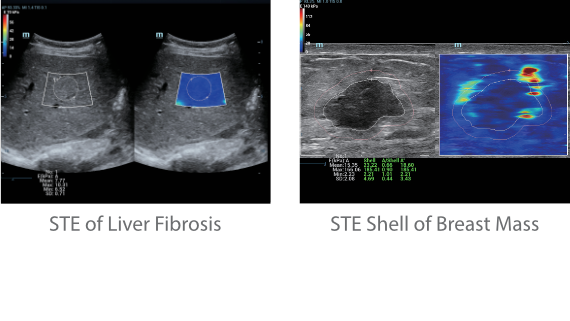

?? Resona 7? ???? ??? ?? ???? ??? ??? ???? ??? ?? ???? V Flow? ?? CNS ??? ?? 3D ??? ???? ?? ???? ?? ??? ?? ?? ?? ??? ??????. ???? ??? ??? ?? ?? ??? ??? ?? ?? ??? ??? Resona 7? ??? ???? ???? ??? ??? ??? ????.